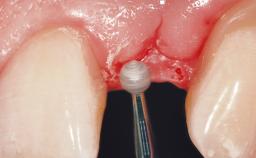

Immediate Flapless Placement of an Implant in a Maxillary Left Central Incisor Site

A 29-year-old female patient presented for treatment to replace the upper left central incisor tooth with an implant- supported restoration. The tooth had been intermittently symptomatic for the previous 12 months. The tooth had originally suffered trauma about 15 years previously. Several endodontic treatments had been performed, including an apicectomy procedure to retain the tooth. The patient was healthy and a non-smoker. She had reasonable expectations in regard to esthetic outcomes and the risk of marginal tissue recession following treatment. At medium smile, the gingival margins of the upper teeth were visible, with a display of 3 to 4 mm of the gingival margins. Gingival recession of tooth 21 and a discrepancy in the gingival levels between teeth 11 and 21 was observable during normal speech and smile.

Placement Protocol | Immediate implant placement |

Tooth Site | Maxillary incisor or canine |

Socket Morphology | Single-root socket |

Socket Integrity | Damage to one or more bone walls |